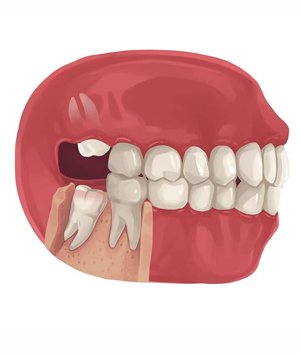

Wisdom Tooth extraction a surgical procedure to remove one or more wisdom teeth , located at the back corners of your mouth on the top and bottom.

• If a wisdom tooth doesn’t have room to grow, results in pain, food entrapment, infection or gum disease, tooth decay infection or other dental problems, you’ll likely need to have it pulled.

• Prevention of potential future problems ,it is recommended for removal if even teeth aren’t currently causing problems.